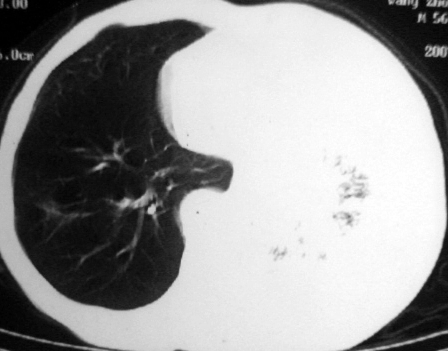

男,54岁,咳嗽,气喘半年,胸痛一月.

血性胸水

左侧胸腔积液 斜裂积液 心包积液 左肺不张 考虑左肺ca并胸膜心包转移。

支持左肺下叶中心型肺癌(累及舌叶)伴阻塞性肺炎、膨胀不全、胸腔积液、心包少量积液。